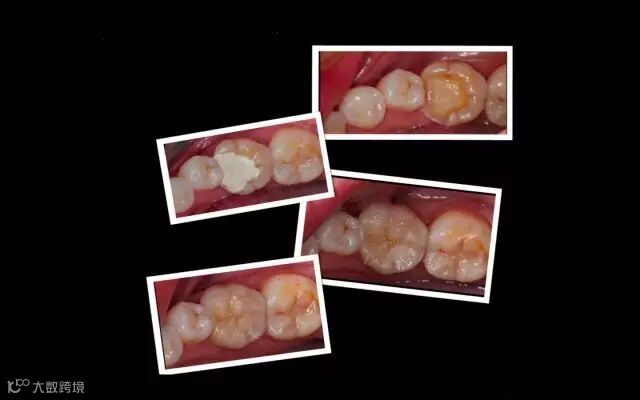

嵌体和传统的补牙不同之处是:嵌体是在口外石膏模型上由专门的牙科技师制作出来的,然后再由临床医生将其戴入患者口内,最终粘固形成的

1、嵌体的整个的制作过程中完全避免了在口腔内部操作的干扰因素。这就使得嵌体的制作比传统的补牙要更精细。技师在制作嵌体的时候,会控制它与牙体的弥合程度,这样就尽可能的避免了牙齿在日后的使用中再次出现龋坏。

2、因为它的整个制作过程是在口外完成的,所以它还可以很好的恢复原来牙齿的外形,恢复原来牙齿的咀嚼效率。而这一点,是传统补牙无论如何都无法比拟的。

这些嵌体,在最终戴如患者口内的时候,真是的非常的完美。在使用上没有任何的影响和不适,而且坚固耐用。

金属嵌体与瓷嵌体的修复对比